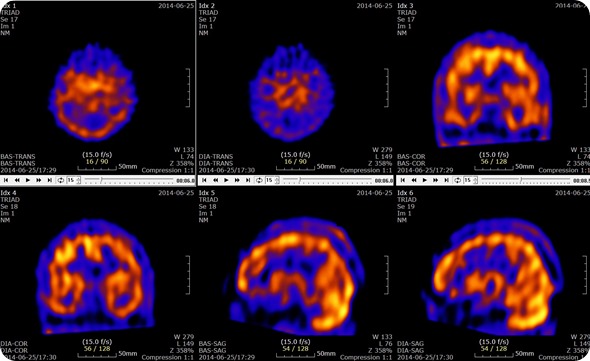

Brain SPECT with Acetazolamide Slices

Brain SPECT with Acetazolamide Slices. Credit: U2em, shared under licenses Creative Commons Attribution-Share Alike 3.0 Unported

SPECT scans are used to determine which parts of the brain are affected by various disorders including Dementia, Epilepsy and head injuries. These are characterized by too much activity in a particular area, too little activity in particular areas or asymmetrical activity across the brain where the activity should be symmetrical. These are all determined through the comparison of the scan results to the standard normal brain scans.